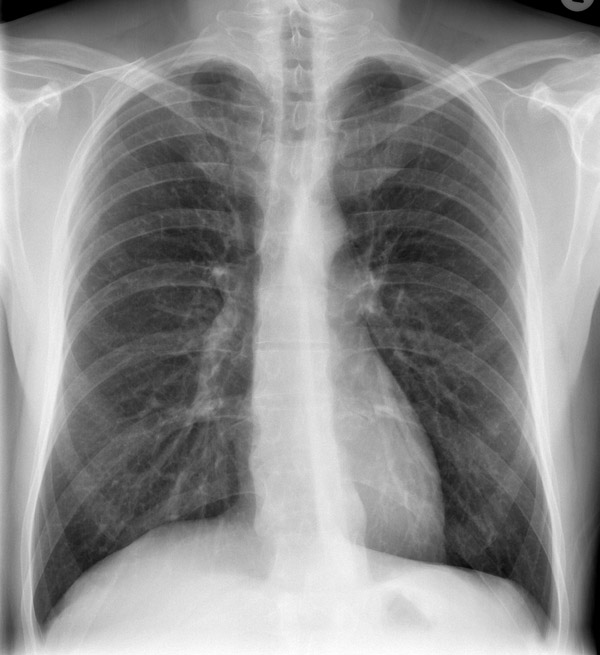

1. Рентгенография органов грудной клетки. Хламидийная пневмония характерна отсутствием рентгеновских признаков (засветов и затемнений) в отличие от бактериальной.

• рентгеновский снимок: локализация в верхнем сегменте левой нижней доли

На рентгене определяются изменения бронхов и легочного интерстиция, а также очаговая, сегментарная или долевая инфильтрация, воспалительные уплотнения, усиление легочного рисунка. Чаще эти изменения обнаруживают с одной стороны в нижних легочных полях.